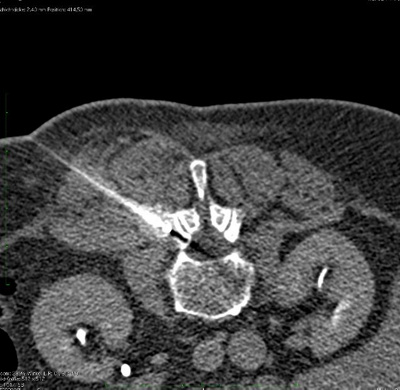

CT-gesteuerte Sondenplatzierung zur Kryoablation eines Weichteiltumors in unmittelbarer Nähe einer lumbalen Nervenwurzel